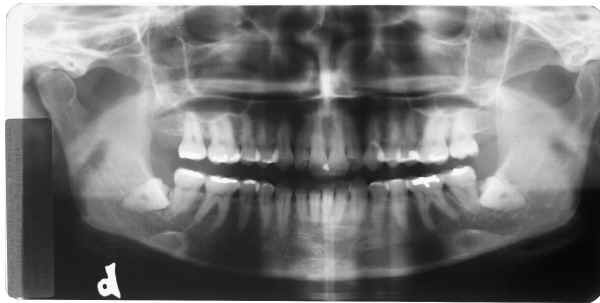

RX superior esquerdo

início

Rx superior direito

Rx inferior esquerdo

Rx inferior direito

Qual destes lados não foi editado?

Responda, justificando, e receba a resposta com as fotos originais!

Matematicamente a probabilidade de erro na 1ª resposta é igual a 75% = 3/4 x 100

Matematicamente a probabilidade de erro na 2ª resposta é igual a 50% = 1/2 x 100

Não aposte sua prova jurídica nisto, responda e verás!

Resposta da Primeira Questão

Radiografia 1

Radiografia 2

Radiografia 3

Radiografia 4